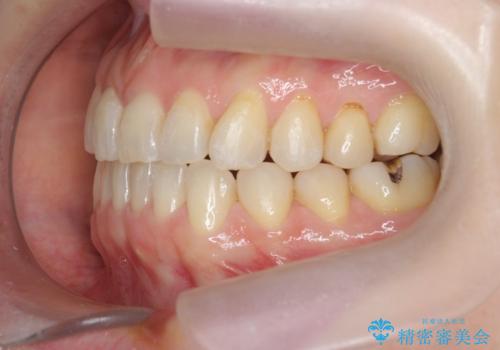

前歯の目立つガタつきをマウスピース矯正で治療

- 大きく傾いてしまった前歯のガタつきの改善を求めて来院されました。

前歯のガタつきをしっかりと取り、機能的・審美的に理想的な歯並びをマウスピース矯正で達成します。

強度のガタつきはマウスピース単体では並び切ることが難しいこともありますが、しっかりと装着していただいたことで良好な治療結果を得ることができました。